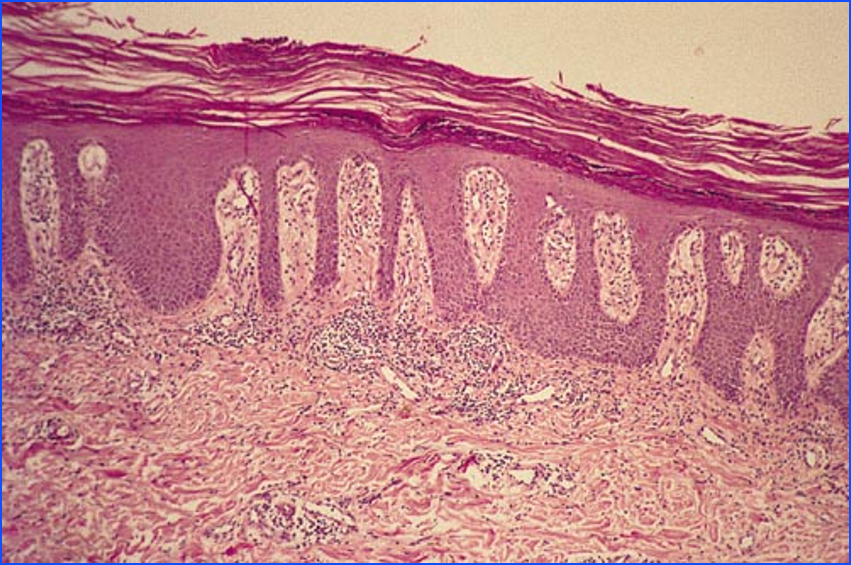

What is the condition shown?

Psoriasis

What condition is shown? what should it look like ?